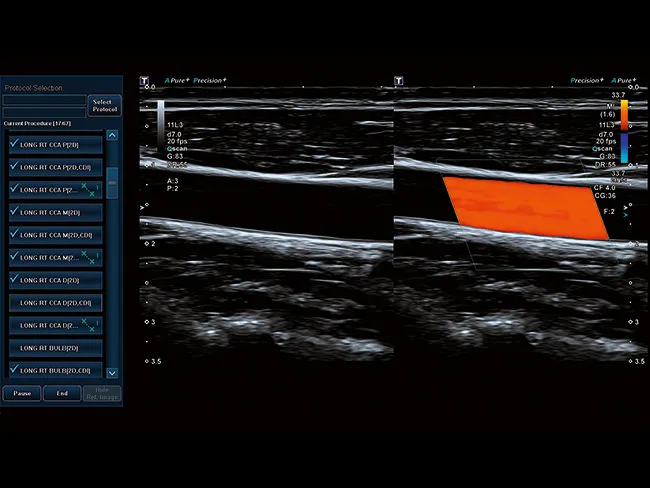

Ассистент по клиническим протоколам Aplio предоставляет надежный метод, обеспечивающий последовательное проведение сложных обследований пациента за пациентом. После активации понятное, легко читаемое меню проведет вас шаг за шагом через весь процесс обследования.